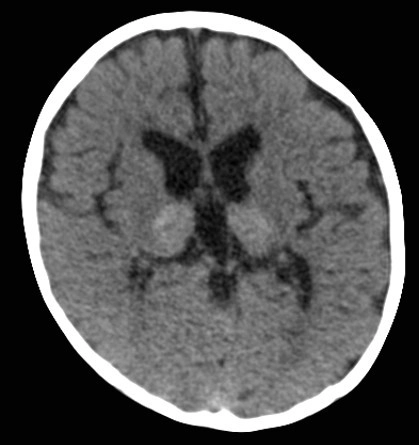

Bệnh não ty thể (Mitochondrial Encephalopathies -ME)

Rối loạn ty thể nguyên phát (Primary mitochondrial disorders - PMDs)

Các biểu hiện ở não của bệnh mucopolysaccharidoses (Cerebral manifestations of mucopolysaccharidoses)

Bệnh loạn dưỡng chất trắng tế bào hình cầu (Globoid Cell Leukodystrophy)/ Bệnh Krabbe

Bệnh Fabry (Fabry Disease)

Rối loạn Peroxisome (Peroxisomal Disorders)/Hội chứng Zellweger (Zellweger Syndrome)

Bệnh nước tiểu mùi si-rô phong (Maple syrup urine disease - MSUD)

Bệnh Canavan (Canavan Disease)

Bệnh loạn dưỡng chất trắng thượng thận liên kết nhiễm sắc thể X (X-linked Adrenoleukodystrophy)

Nhiễm toan glutaric type 1 (Glutaric aciduria type 1)

Bệnh Loạn dưỡng chất trắng thể não to kèm nang dưới vỏ (Megalencephalic Leukoencephalopathy with Subcortical Cysts - MLC)

Thoái hóa thần kinh với tích tụ sắt trong não (Neurodegeneration with Brain Iron Accumulation - NBIA)

Thoái hóa thần kinh liên quan đến Pantothenate Kinase (Pantothenate kinase-associated neurodegeneration - PKAN)

Huntington Disease - HD

Bệnh loạn dưỡng chất trắng dị sắc (Metachromatic Leukodystrophy - MLD)

Bệnh Wilson- Biểu hiện ở não bộ (Wilson Disease)